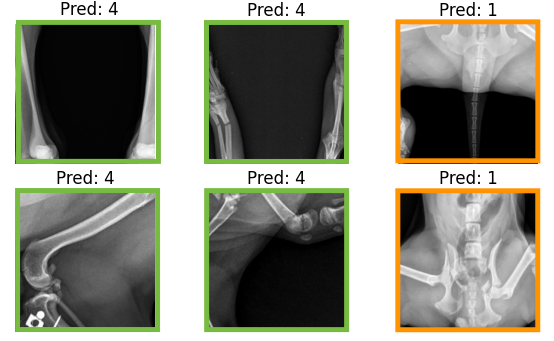

Increased interpretability of the results

To obtain a more holistic understanding of model performance, we use 6 major visual features identified during data analysis as a guide for understanding the model’s decision-making process. Figure 5 displays the performance of the clustering system on example-saliency crops with each one of the major visual features.

All of the saliency crops selected as representative of vertical lines were assigned by the KNN to cluster 2, and all the horizontal lines to cluster 5, along with most oblique lines. Interestingly, different views of medical devices appear to be clustered separately, with frontal views of the plate found in cluster 3 and crops containing the screws in cluster 0. The zoomed out crops, which mostly represent aberrant mistakes, are found in cluster 4. Finally, the crops without lines are mostly found in cluster 1.